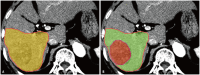

Yttrium-90 transarterial radioembolization (TARE) has emerged as a valuable treatment option for hepatocellular carcinoma (HCC) and is being increasingly incorporated into clinical guidelines. Recent advancements in dosimetry, including personalized dosimetry and multi-compartment modeling, have significantly improved tumor response and clinical outcomes. Although high tumor-absorbed doses are associated with better oncologic control, careful dose adjustment is essential for minimizing toxicity to normal liver tissue and lungs. This review explores the key aspects of TARE dosimetry, including single- and multi-compartment modeling, differences between resin and glass microspheres, dose-response relationships, and strategies to mitigate hepatotoxicity and radiation pneumonitis. Various clinical applications of TARE have been discussed, ranging from curative-intent radiation segmentectomy and lobectomy to palliative treatment of diffuse and macrovascular invasion-associated HCCs. In South Korea, where cadaveric liver transplantation is limited, a multidisciplinary approach is particularly important for optimizing treatment strategies and preserving liver function for potential future interventions. As dosimetry continues to evolve, further research is required to refine dose optimization protocols and validate their clinical impact in different patient populations, including those in South Korea.